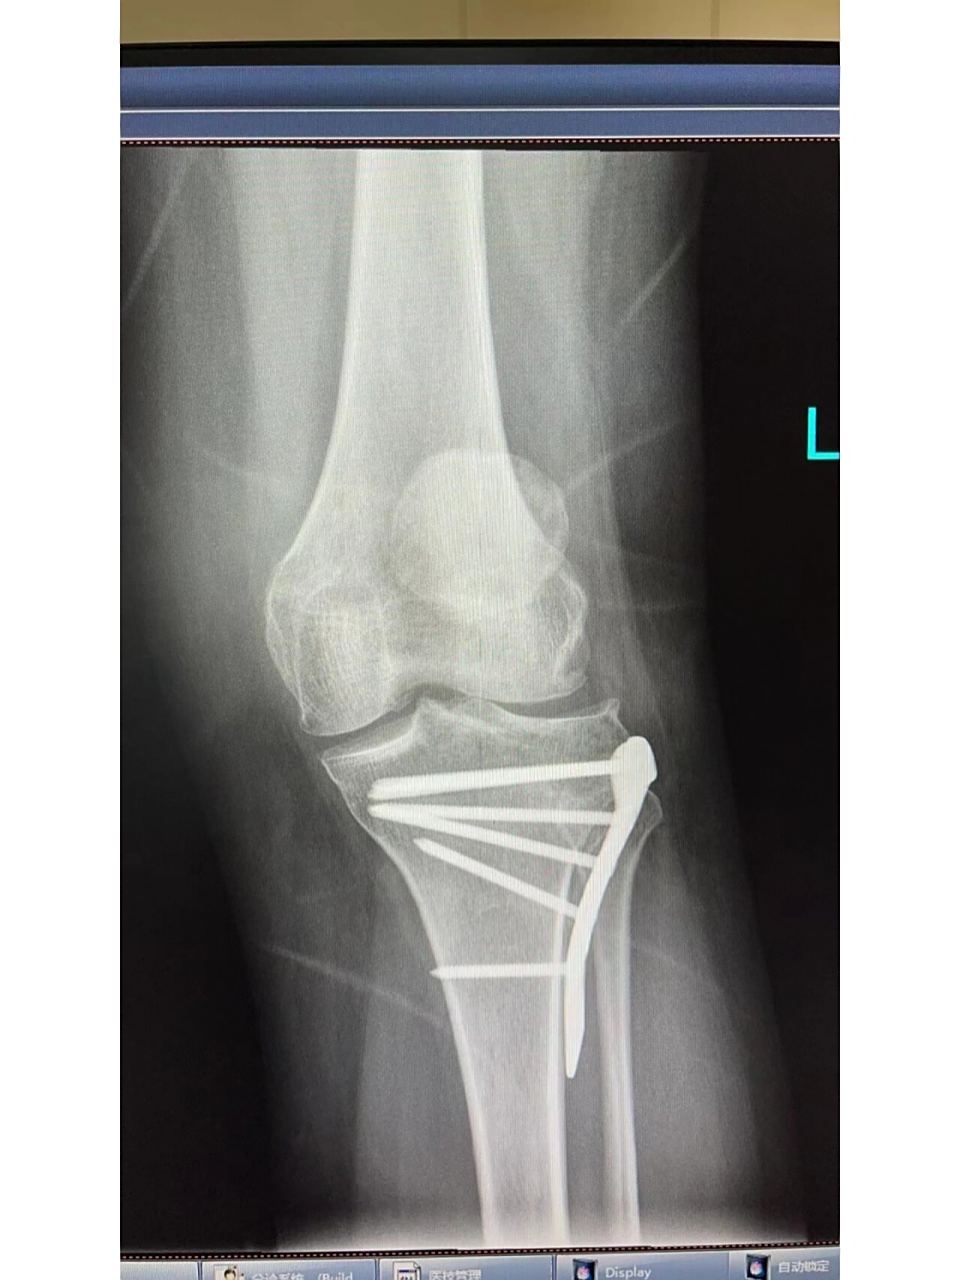

4、对于胫骨平台骨折是否能不进行手术,这个问题必须根据具体病情,特别是根据膝关节的CT片来判断,常见判断如下1需要手术胫骨平台骨折常见于比较严重的车祸伤,绝大部分的患者都需要手术治疗一般来说,如果骨折断端塌陷5mm以上,就需要手术,特别是有重要韧带软组织损伤,以及其他胫骨平台骨折严重类型。

8、手术方法可以采用膝关节镜进行微创手术,这是一种创伤小恢复快的手术方法在手术中,给予骨折部位复位,确保骨折块回到正确的位置然后采用钢丝进行内固定,以保持骨折部位的稳定性,促进骨折愈合总结左侧胫骨髁间嵴骨折的治疗方法应根据骨折的移位情况来选择对于无大移位的骨折,可以采取保守治疗。